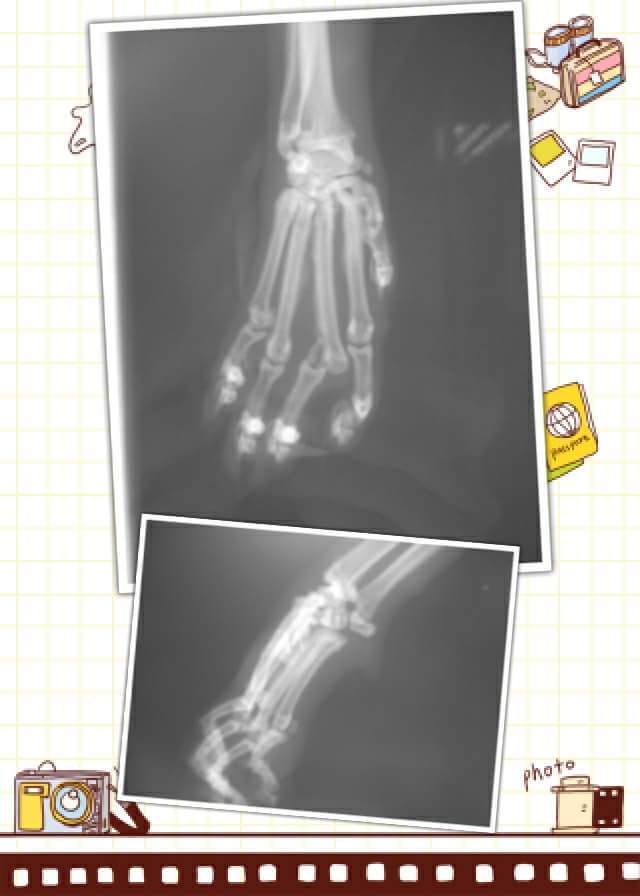

主題: 左腳跛腳,左眼角小擦傷的咪咪 申請者姓名: 張俞兒 花色: 申請日期: 2017-04-26 19:41:00 申請者部落格: 申請者臉書網址: sammiping2011@yahoo.com.tw 所在縣市/合作醫院: 高雄市/樂生動物醫院 治療費用: 10200元 需求人數: 23人 已結案 (2024-06-01 13:30:06) 報名人員: pamylucky(已付款)、pamylucky、show(已付款)、Rachel Hsieh x2(已付款)、Celine Lin(已付款)、Jane Liao x3(已付款)、陳昱先 x4(已付款)、Bella Chiang(已付款)、vivian(已付款)、白婷(已付款)、Fan x2(已付款)、Emily Chou x6(已付款)、 候補人員: 動物病情說明: 咪咪是我新家附近餵養區的貓,某天咪咪連3天都沒出來吃飯,第四天出現時左腳很腫很跛,左眼角有擦傷,心想不知道是被車撞還被車壓到,當天就先投藥,投了幾天腳一樣是跛的,就誘捕到醫院。

醫生檢查後,發現咪咪左前腳掌骨斷裂一根,有脫水及肝指數(ALKP)略高,目前已先給藥及輸液治療,骨折的部分可採外固定或籠飼限制活動休養,靜待骨頭自行癒合。(醫生說如果是斷3根就需要手術,但1根醫生評估是不用手術)

6. X光片 400*2= 800